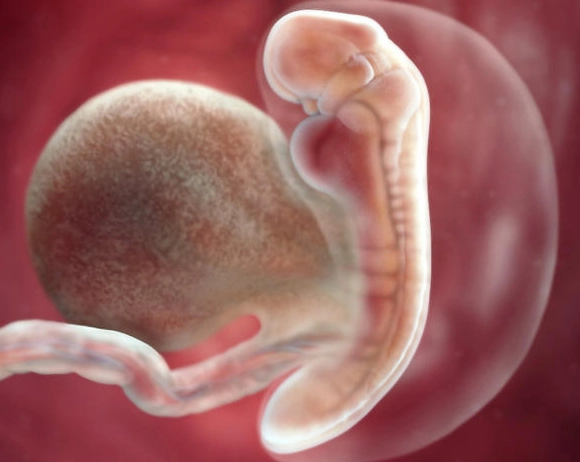

At 5 weeks, an ultrasound (usually transvaginal for clarity) might seem early, but it can show important structures:

- Gestational Sac: A small, black, fluid-filled circle within the uterus. This confirms the pregnancy is intrauterine (not ectopic).

- Yolk Sac: Often visible by the end of the 5th week. It nourishes the embryo before the placenta takes over. Seeing it is a very good sign.

- Fetal Pole: The first visual evidence of the developing embryo. It may be visible as a tiny thickening on the edge of the yolk sac.

Don't panic if you don't see a heartbeat yet. It typically becomes visible around 6 weeks. The absence of a heartbeat at 5 weeks is not a sign of an unhealthy pregnancy.